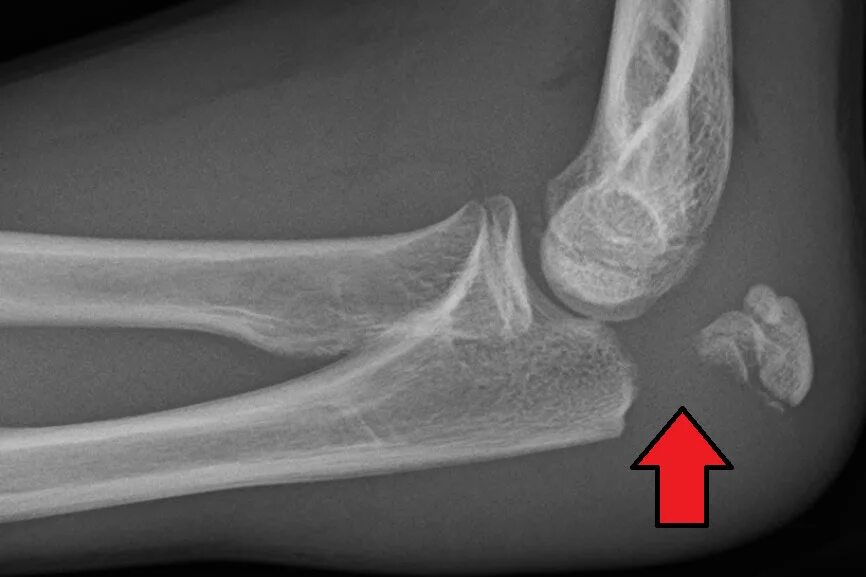

Перелом смещение локтя